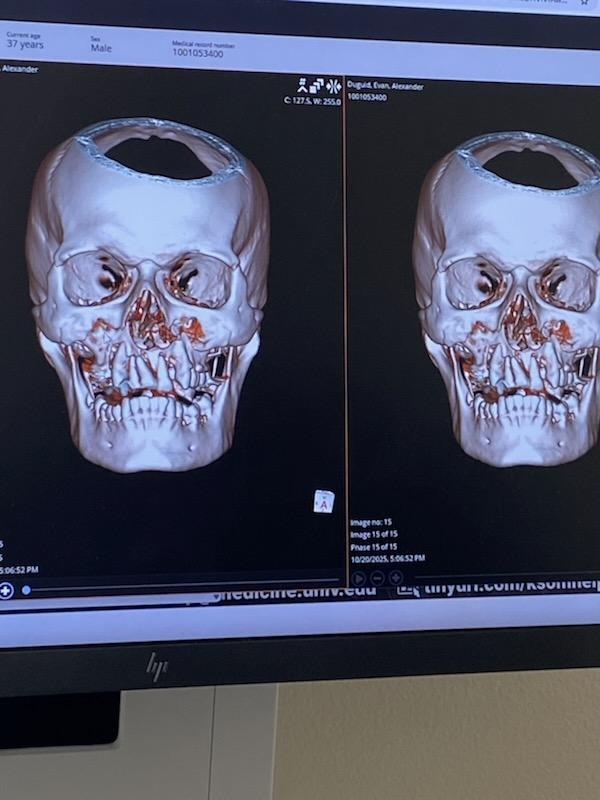

My name is Evan. On 10/20/2025, I was hit by a Tesla Model 3 while riding my motorcycle in Las Vegas. The impact was violent enough that I was rushed into TICU and underwent three life-saving surgeries. I survived, but only barely.

My injuries were catastrophic:

• My lower skull broke from both sides of my face separating the top from bottom.

• All my upper teeth were broken or had to be removed

• My palate completely broke off

• My nose broke and shifted

• My helmet shattered at the visor and mouth area